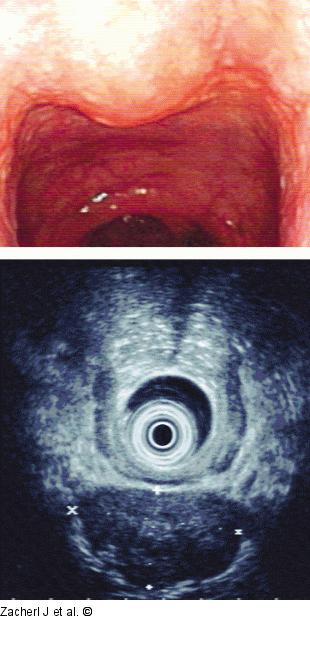

Abbildung 1: Submukosaler Tumor Endoskopischer und endosonographischer Aspekt des SMT 2005 |

Abbildung 1: Submukosaler Tumor

Endoskopischer und endosonographischer Aspekt des SMT 2005 |